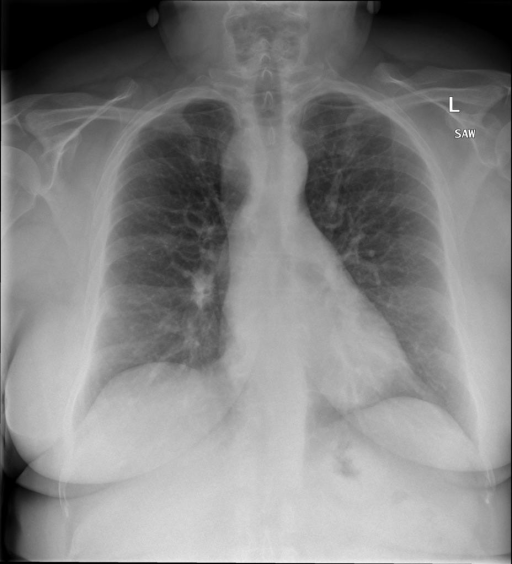

|X光影像|诊疗报告(医生)|XrayGLM|

||心影形态在正常范围内。没有急性骨质异常。有可能出现没有明显的吸水或肺实质状况的线索。没有大面积积液或气胸。有可能怀疑其有误吸或肺实质问题。为了确诊和治疗,可能需要进行适当的影像学随访。|心脏大小正常,肺部和纵隔轮廓清晰。没有急性异常或活动受限的证据。没有任何明显的气胸、胸腔积液或肺不张的迹象。此外,也没有发现任何局灶性骨质异常或其他急性疾病。|